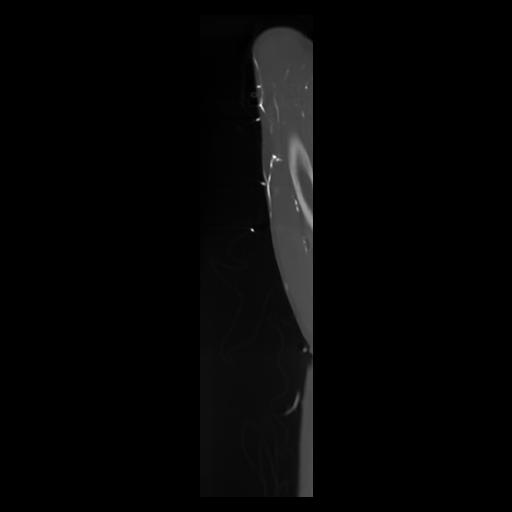

30 CUERPO,CE,Sagittal,3.000,CUERPO,Sagittal,